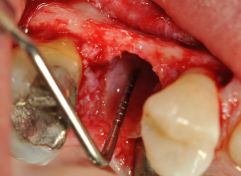

SCOLLAMENTO CON EVIDENZIZAZIONE DEL RESIDUO RADICOLARE

RADICOLOPLASTICA PIEZOELETTRICA PER PRESRVARE PIù OSSO POSSIBILE

TAGLIO DELL'ANCHILOSI VESTIBOLARE A SPESE DEL CEMENTO RADICOLARE